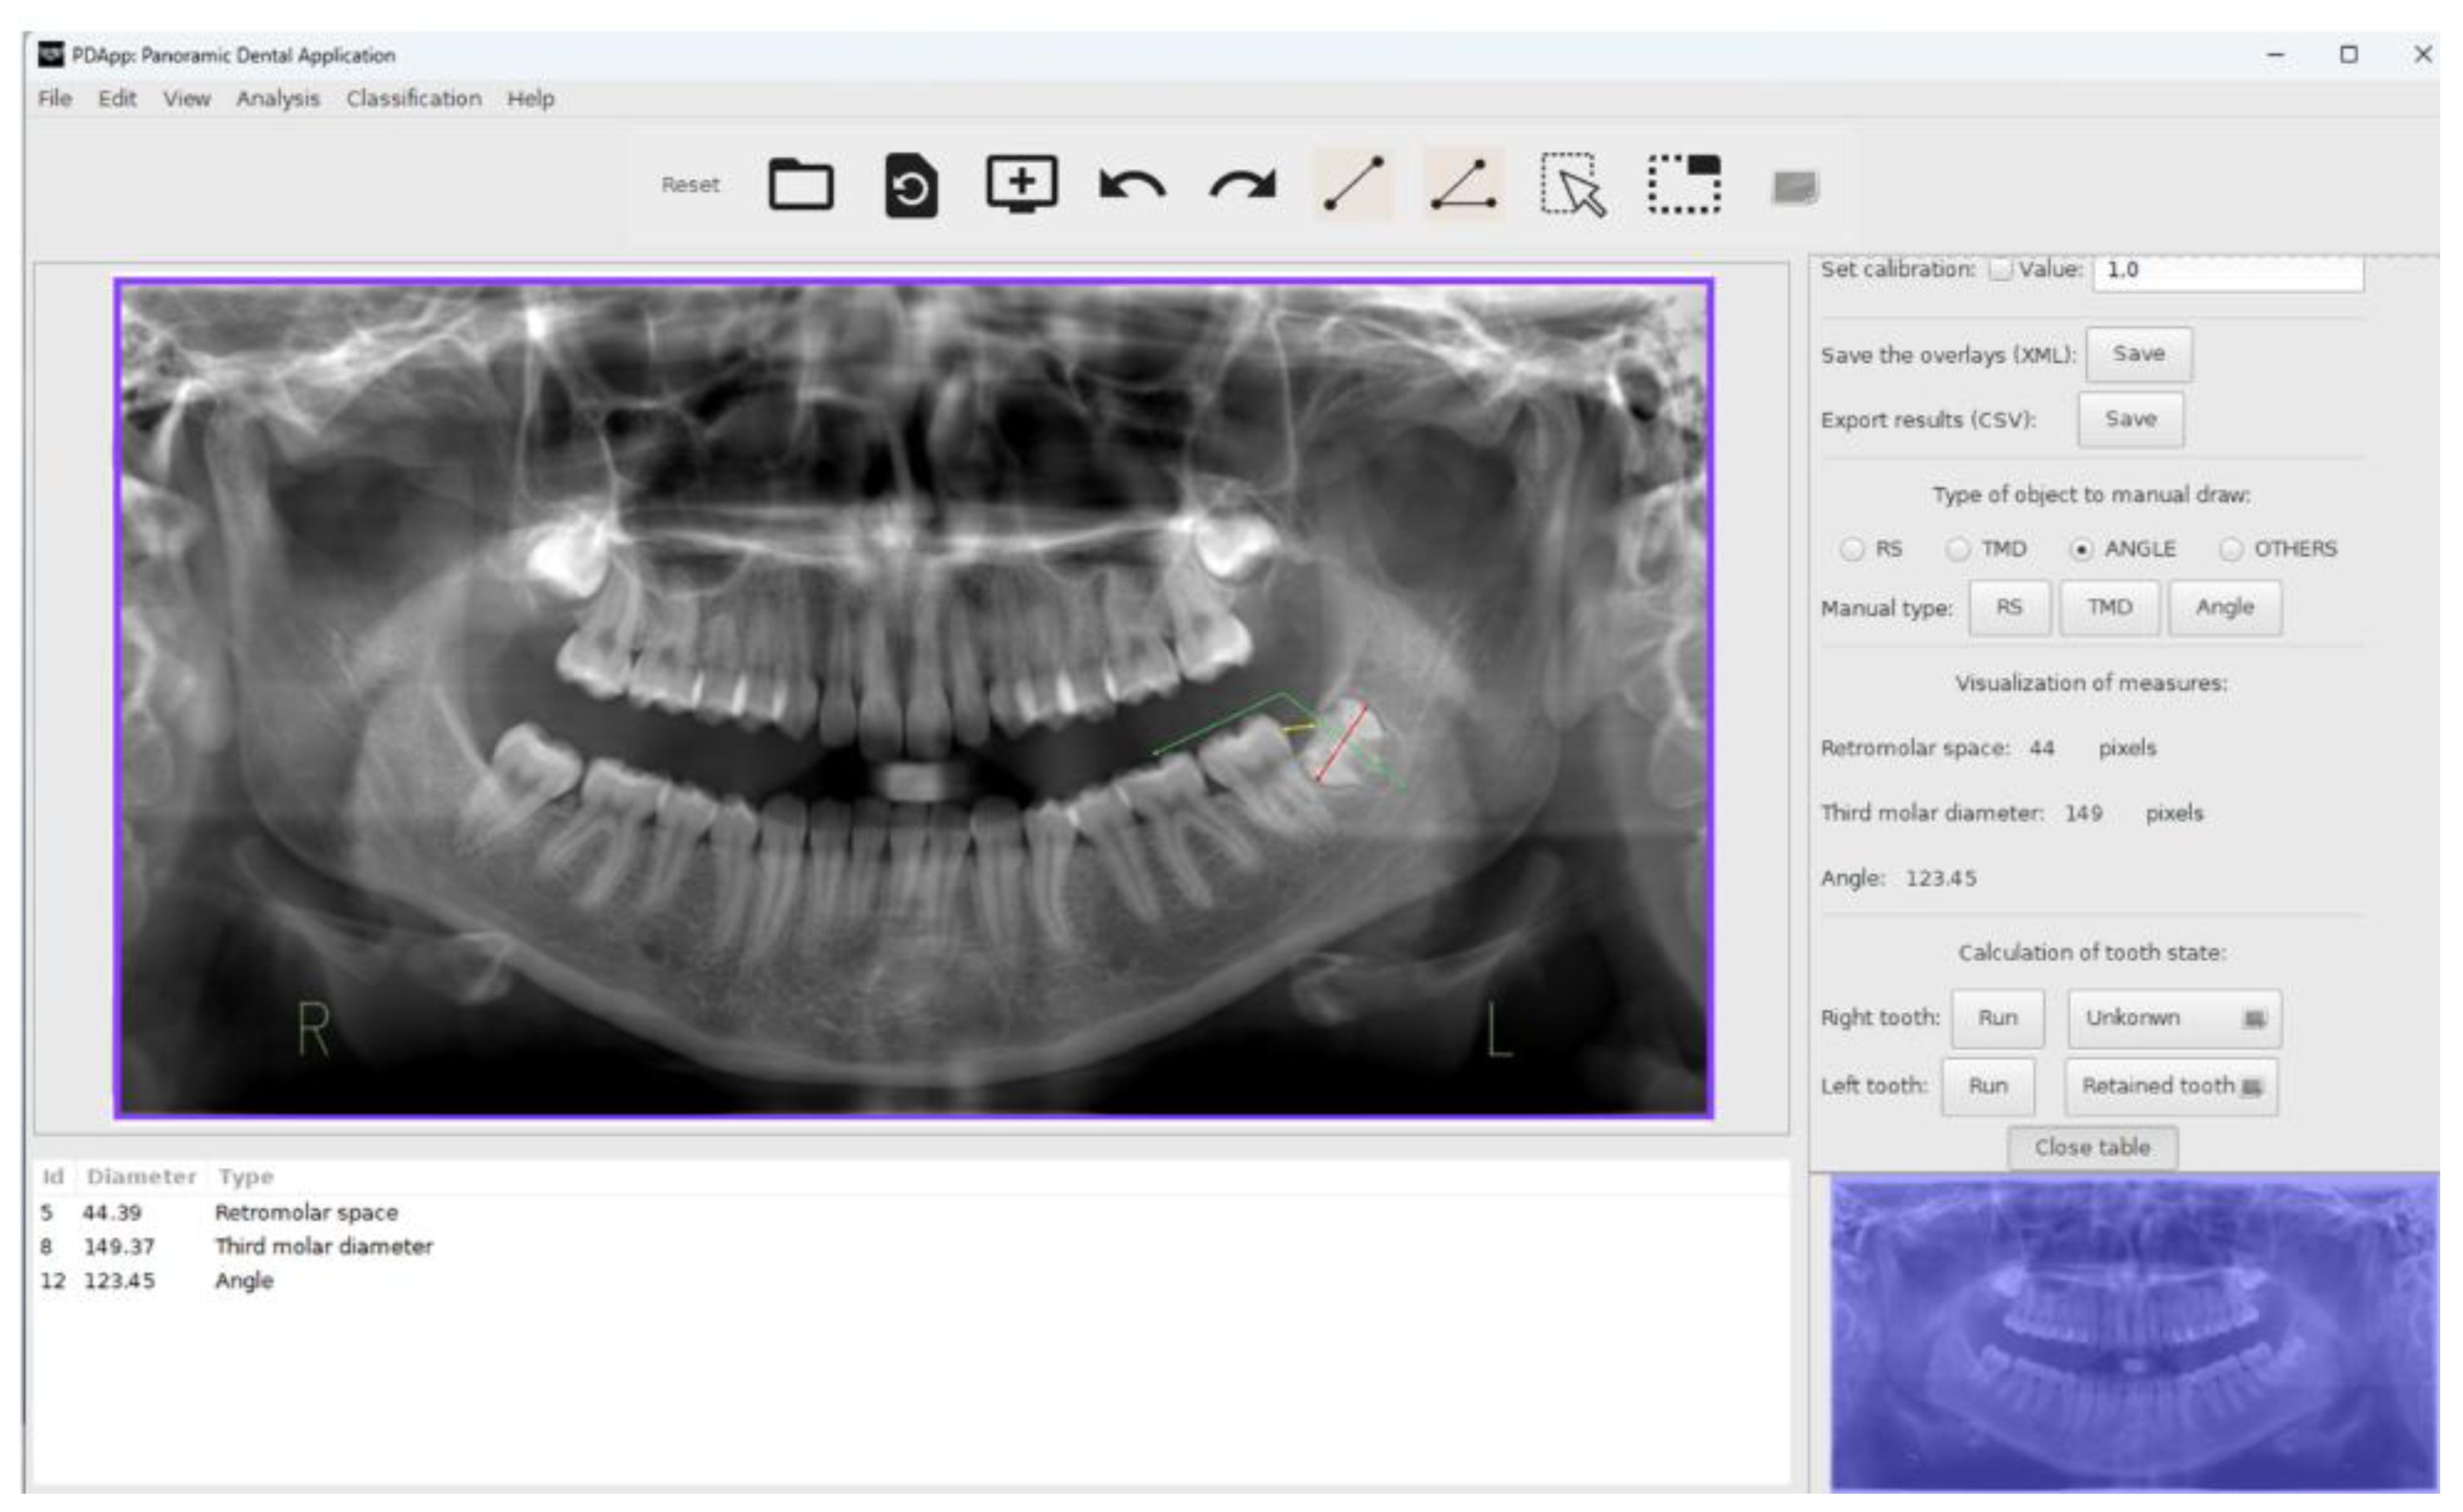

PDApp is a desktop application that runs on a general-purpose computer under the Linux and Windows operating systems. It has been written in the C++ programming language using the GTK+ (GIMP Tool Kit) library1 to develop the GUI. Figure 1 shows the GUI of PDApp with a typical radiological image loaded, processed and reviewed by the expert, and with the lateral panel displayed.

Figure 1. Screenshot of the software PDApp with a panoramic radiography analyzed and the lateral panel opened. In the left molar, the red line represents the third molar diameter, the yellow line the retromolar space and the green lines the angle. The measures of the right molar are shown in the lateral panel.